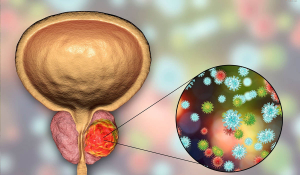

Рак Передміхурової Залози: Симптоми, Діагностика та Лікування у Івано-Франківську

Серед великої кількості онкологічних захворювань, рак передміхурової залози залишається серйозною загрозою для здоров'я чоловіків. За статистикою, цей вид раку є одним з найпоширеніших. Однак рання діагностика може змінити хід подій та зберегти життя.

Фактори ризику розвитку раку передміхурової залози: